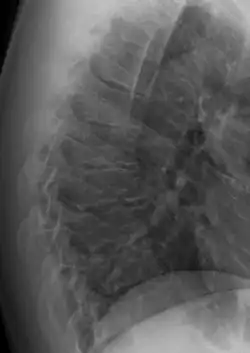

Scheuermann's disease

| Scheuermann's disease on lateral Xray of the T spine | |

Scheuermann's disease is a skeletal disorder.[3] It describes a condition where the vertebrae grow unevenly with respect to the sagittal plane; that is, the posterior angle is often greater than the anterior. This uneven growth results in the signature "wedging" shape of the vertebrae, causing kyphosis. It is named after Danish surgeon Holger Scheuermann.[4][5][6]

Scheuermann's disease is considered to be a form of osteochondrosis of the spine. It typically develops during adolescence and presents a significantly worse deformity than postural kyphosis. Patients with Scheuermann’s kyphosis cannot consciously correct their posture. The apex of their curve, located in the thoracic vertebrae, is quite rigid.

In addition to the pain associated with Scheuermann's disease, many individuals with the disorder have loss of vertebral height, and depending on where the apex of the curve is, may have a visual 'hunchback' or 'roundback'. It has been reported that curves in the lower thoracic region cause more pain, whereas curves in the upper region present a more visual deformity. Nevertheless, it is typically pain or cosmetic reasons that prompt sufferers to seek help for their condition. In studies, kyphosis is better characterized for the thoracic spine than for the lumbar spine.[7][8]

The seventh and tenth thoracic vertebrae are most commonly affected. It causes backache and spinal curvature. In very serious cases it may cause internal problems and spinal cord damage. The curvature of the back decreases height, thus putting pressure on internal organs, wearing them out more quickly than the natural aging process; surgical procedures are almost always recommended in this case.